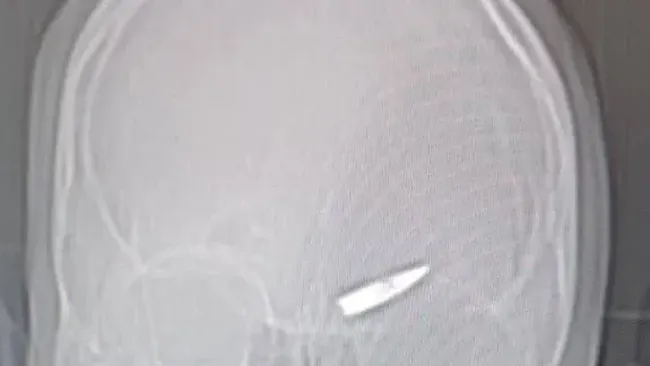

Setelah melakukan pemeriksaan sinar-X untuk mencari serpihan peluru, dokter Rusia menemukan peluru senapan besar yang tertancap di otak prajurit tersebut.

Mereka menganggap kasusnya sebagai mukjizat yang langka, dan kini pria itu dipuji atas ketangguhannya. Beberapa bahkan meminta militer Rusia untuk menghormatinya dengan medali.